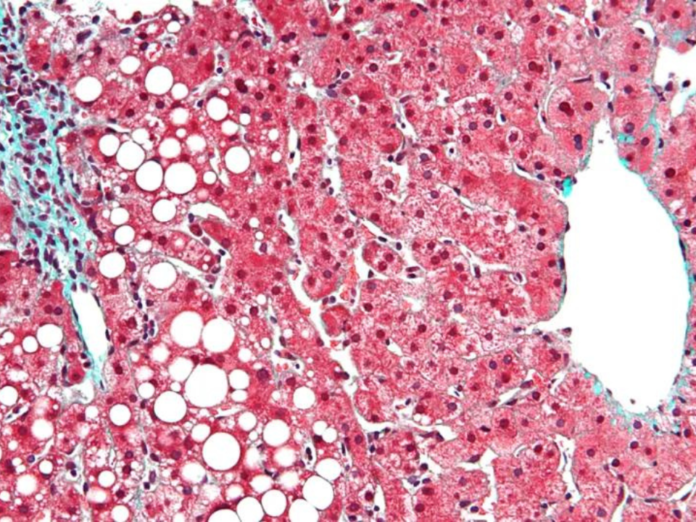

Pesquisa desenvolvida pela Faculdade de Medicina (FMUSP) mostrou que há uma associação importante entre o aumento dos níveis de ácido úrico sérico e a doença hepática gordurosa não alcoólica (DHGNA). A DHGNA é causada pelo acúmulo progressivo de gordura no fígado e não pelo consumo excessivo de álcool. Nos últimos anos, evidências clínicas sugerem que o ácido úrico elevado frequentemente está associado ao desenvolvimento ou progressão da DHGNA. Altos índices de ácido úrico podem levar ao desenvolvimento de resistência à insulina (RI).

A doença hepática gordurosa não alcoólica vem se tornando uma das principais causas de doença hepática crônica no mundo. Sobrepeso, diabete, má nutrição, perda brusca de peso e sedentarismo estão entre os fatores de risco para o aparecimento da doença.

Há evidências de que a pressão alta, resistência à insulina, níveis elevados de colesterol e triglicérides estão diretamente associados ao excesso de gordura no fígado.

Estudos mostram que, entre os pacientes com esteatose hepática simples, 12% a 40% desenvolverão NASH (forma mais avançada da doença hepática gordurosa não alcoólica) com fibrose precoce após oito a 13 anos. Desses, aproximadamente 15% desenvolverão cirrose e/ou evidência de descompensação hepática no mesmo período. Cerca de 7% das pessoas com cirrose compensada associada à DHGNA vão evoluir para câncer no fígado dentro de dez anos, enquanto 50% exigirão um transplante ou morrerão de causa relacionada ao fígado.